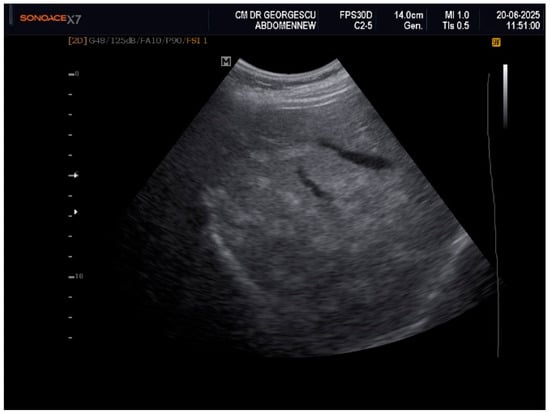

Liver Lipodystrophy in Barraquer–Simons Syndrome: How Much Should We Worry About?

Lipodystrophy is a rare group of metabolic disorders characterized by the abnormal distribution of body fat, which can lead to various metabolic complications due to the body’s inability to adequately process carbohydrates and fat. We report the case of a female, aged 53 years, who was admitted as an outpatient for progressive weight loss of the upper part of the body (face, neck, arms, and chest), dyspeptic complaints, fatigue, mild insomnia, and anxious behavior. Her medical history was characterized by the presence of dyslipidemia, hypertension, and a minor stroke episode. However, she denied any family-relevant medical history. Although the clinical perspective suggested a possible late onset of partial acquired lipodystrophy, due to the imaging exam that revealed an enlarged liver with inhomogeneous structure with multiple nodular lesions, scattered over both lobes, a lot of lab work-ups and complementary studies were performed. Eventually, a liver biopsy was performed by a laparoscopic approach during cholecystectomy, the histology consistent with metabolic disease-associated steatohepatitis (MASH). In conclusion, given their heterogeneity and rarity, lipodystrophies may be either overlooked or misdiagnosed for other entities. Barraquer–Simons syndrome (BSS) may be associated with liver disease, including cirrhosis and liver failure. Liver lipodystrophy in BSS may sometimes feature steatosis with a focal, multi-nodular aspect, multiplying the diagnostic burden. Liver lipodystrophy may manifest as asymptomatic fat accumulation but may progress to severe conditions, representing one of the major causes of mortality in BSS, apart from the cardio-vascular comorbidities. Given the potential of severe outcomes, it is mandatory to correctly assess the stage of liver disease since the first diagnosis. Full article

Figure 1